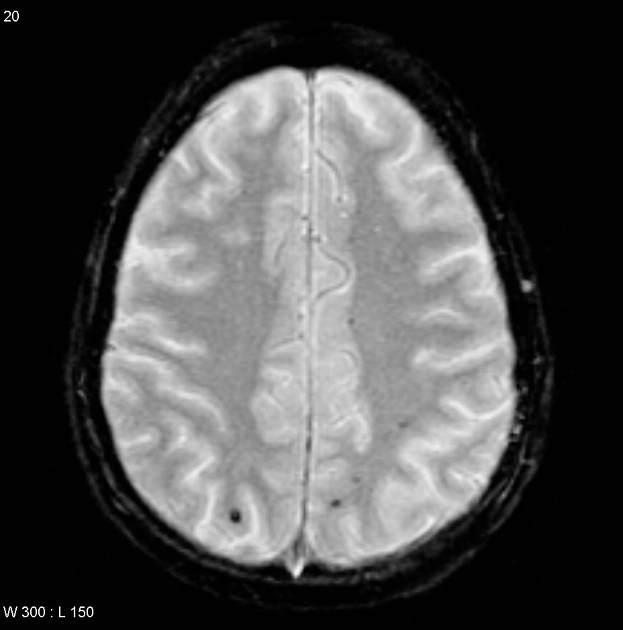

Tổn thương sợi trục lan tỏa (Diffuse Axonal Injury - DAI)

16/03/2026